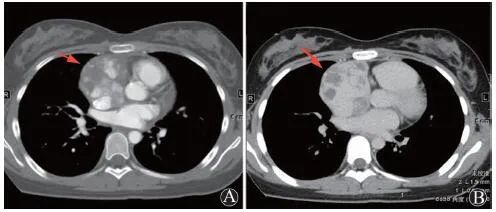

患者入院行心电图为窦性心律、律齐,肢体导联低电压表现。行胸部CT提示右侧胸腔大量积液,右肺膨胀不全,双肺散在索条、斑片、淡片影。床旁超声心动图见大量心包积液(图1 ),遂行心包穿刺置管引流术(经心尖入路),引流液为暗红血性液体,送检引流液常规:外观血性混浊,比重1.030,细胞总数1 852 020×106/L,白细胞总数995×106/L,单核55%,多核45%,黎氏试验阳性;引流液生化:总蛋白(TP)44 g/L,白蛋白(Alb)29 g/L,LDH 496 U/L,ADA 9.7 U/L,葡萄糖(Glu)4.7 mmol/L。同时,该引流液测得血红蛋白(Hb)69 g/L。同期外周血Hb 124 g/L,而引流后次日下降至90 g/L。引流3 d后查体发现左下肺呼吸音低,叩诊呈浊音,行胸部X线片提示左肺新发胸腔积液,未见气胸表现。

A:胸骨旁长轴平面;B:心尖四腔心平面

图1 患者入院后床旁超声心动图可见大量心包积液(箭头所示)